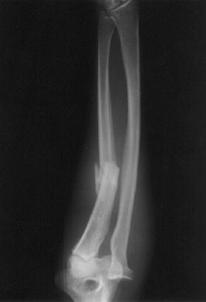

Fracturi simple: SPIRALA OBLICA TRANSVERSALA

Fractura spirala de Fractura transversa de diafiza femurala Fractura spirala de diafiza tibiala

diafiza humerala

Fractura spirala de diafiza tibiala Fractura oblica de diafiza tibiala Fractura transversala de diafiza tibiala

Fracturi cominutive

Fracturi spirala cominutive de Fractura complexa de diafiza radiala diafiza humerala